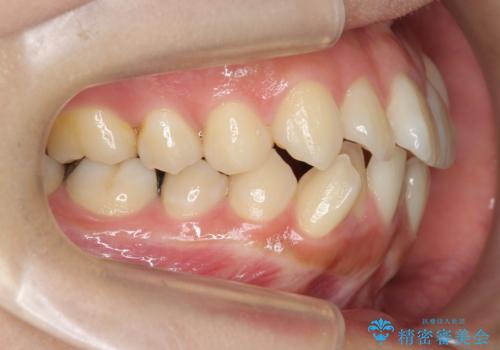

八重歯を矯正治療で治したい!

- 八重歯・がたつきのある歯並びの改善を求めて来院されました。

全部の歯が入り切るスペースがなかったため、小臼歯4本を抜去しワイヤーを用いたマルチブラケット矯正を選択しました。